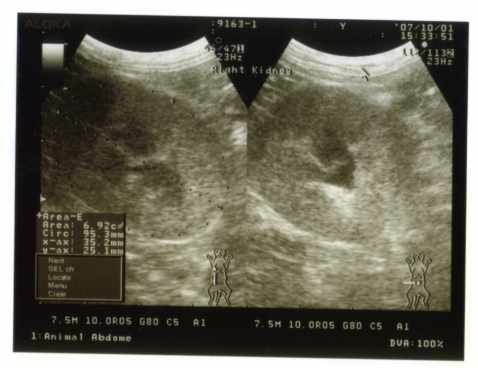

■エコー

・腎臓

右が肥大しており、左はやはり小さく萎縮している(ほぼ機能ははたしていないであろう)

前回(2007/1)から大きさ構造に変化は見られず

がんばって右の腎臓にて維持をしている様子

大切に守ってやらねばならない

右